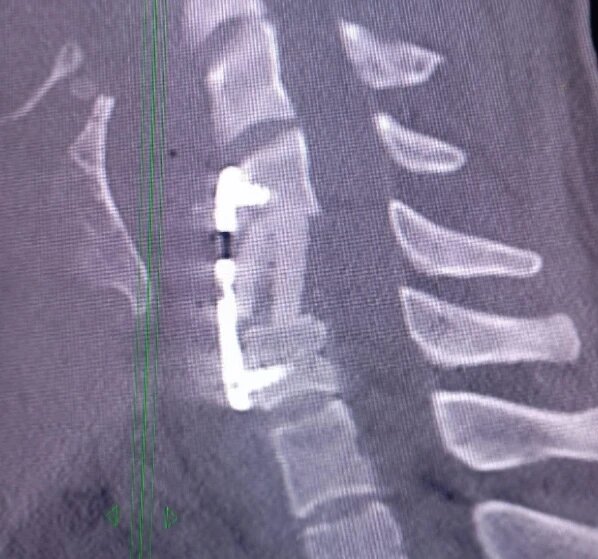

Врачи Осолодченко и Исмаилов провели сложную операцию. Они убрали сломанный фрагмент позвоночника, установили вместо него имплант и зафиксировали титановой пластиной.

Пациент очень быстро встал на ноги и через две недели был выписан из больницы.